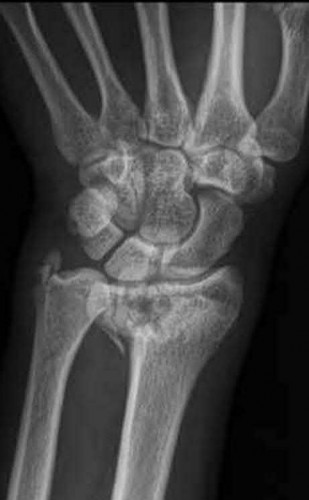

Question 6

A 22-year-old male falls onto an outstretched hand and sustains a displaced fracture through the proximal pole of the scaphoid. Avascular necrosis of the proximal pole is highly likely due to the disruption of its primary vascular supply. Which vessel provides this critical retrograde perfusion?

Explanation

The primary blood supply to the scaphoid is from the dorsal carpal branch of the radial artery, which enters the dorsal ridge of the scaphoid at the waist and courses proximally. This retrograde blood flow makes proximal pole fractures highly susceptible to avascular necrosis and nonunion. The superficial palmar branch provides a minor supply (about 20%) to the distal pole.